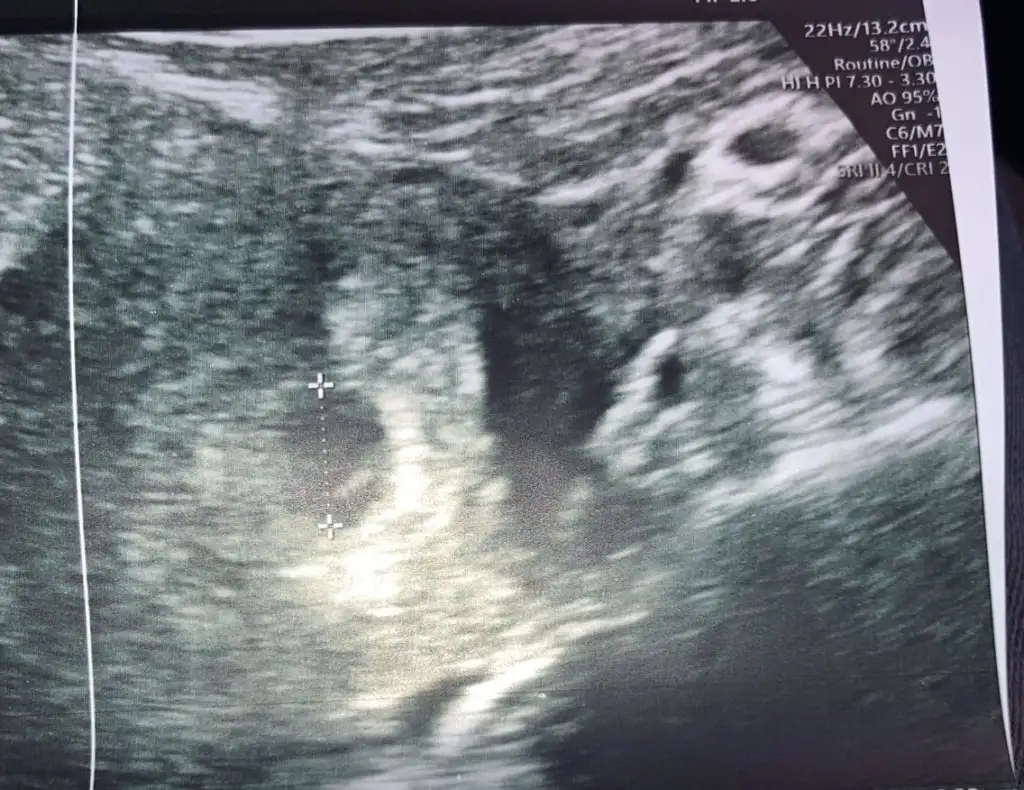

Merhaba kızlar.. regl olmam gereken tarih 22 Ağustos ama ben vücudumda ki değişimi fark edip reglden 1 gün önce test yaptım silik çıktı,22 Ağustos kan verdim hcg 40 çıktı başlangıç dediler,ağır işte çalıştıgim için işi durdurdum 25 Ağustos 138 29 Ağustos 902 çıktı,bu zaman dan sonra kan vermeyi bıraktım jinekologum tatildeydi onu bekledim 3 gün önce pembe lekelenme ile acile gittim kan aldılar 20binler de dedi doktor Alttan muayene etti şuan 2.ci aşamadasınız kese oluşmuş dedi..çok korkuyorum ve stresliyim..çocuk oluşmazsa kalbini duymazsam diye jinekolog da acilde ki doktor da 20 Eylül de belli olur dolu kese mi boş kese mi dedi. geç döllenme falan mi?? Son kan verdiğim tarihle 3 gün önce ki arasında 14 gün var neden yeni oluştu acaba kese ve neden boş uygulamaya göre 6+0 haftalıktı gittiğim de.

Bana da bugün 7 haftalık görüntümde bos gebelik olabilir çünkü içinde beyaz çizgi var bu istemediğiniz bir şey dedi. Bebek yok kese icinde de beyazlık var vakumla alırız 1 hafta bekleyelim dedi katacağını bilemedim yarin gideceğim başka yere yine başına gelen var mı su go4untu ne demek bekleyemiyorum yarına dek